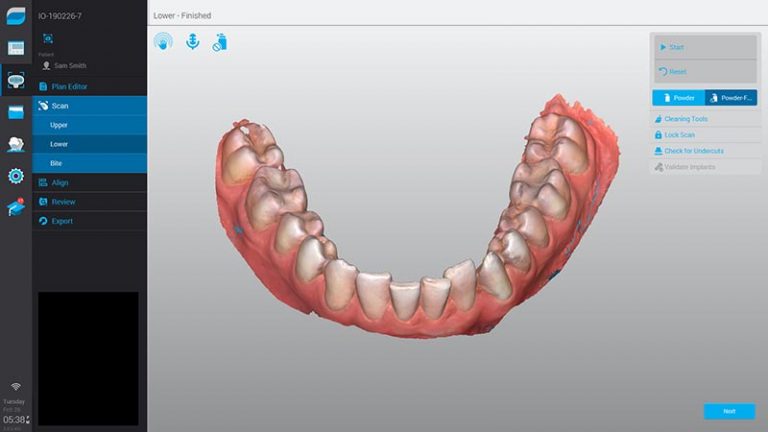

Nosso Scanner elimina algumas etapas clínicas e ainda evita possíveis erros de distorções, garantindo mais precisão para o seu processo.

Com nossa tecnologia a confecção de aparelhos, lentes de contato e até mesmo próteses é extremamente simples, eliminando completamente a necessidade da moldagem.

Em apenas alguns minutos todas as informações necessárias são coletadas, sem nenhum processo desconfortável.

Resultados em tempo real são prontamente enviados e analisados pelos profissionais responsáveis, reduzindo drasticamente o tempo necessário para as próximas etapas.